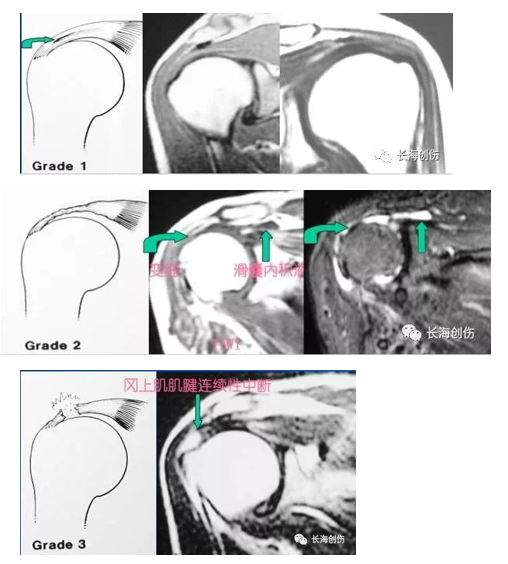

MRI 分级:0 级:正常的肩袖韧带在MRI上为均匀的低信号,是肌腱的延续;1 级:又称肌腱炎,这时肩袖的连续性是完整的,但是在冈上肌肌腱内见信号的增高。1 级的信号改变在质子加权图像中显示最为清晰,为中等信号。这种信号的改变最为可能是由于水肿、炎症反应和出血所引起的;2 级:T1WI或PDWI上见有信号增高并见肩袖的变细或不规则,滑囊内通常有积液;3 级:T2WI上信号增高涉及整个肌腱,肌腱连续性中断,滑囊内多有积液。